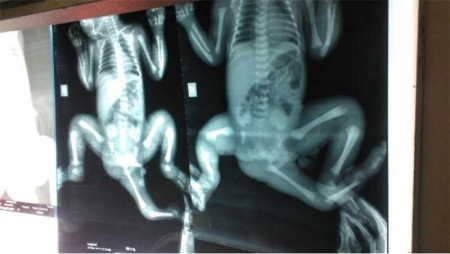

গাজীপুর থেকে তিন পায়ের এক শিশু ঢাকা মেডিক্যালে আসে। তারপর নানা পরীক্ষা নিরীক্ষা আর দফায় দফায় অপারেশন। এক পর্যায়ে সবাই হতাশ। কর্তৃপক্ষ জানিয়ে দিল দেশের চিকিৎসা ব্যবস্থার সীমাবদ্ধতায় আর কিছুই করার নেই।

অস্ট্রেলিয়া ও ইউরোপের ডাকসাইটে প্রায় ৬০ জন বিশেষজ্ঞ চিকিৎসক ও সার্জন যোগ দেন চৈতির চিকিৎসায়।গত ১৪ নভেম্বর প্রথম ধাপের সফল অস্ত্রোপচার হয় চৈতির শরীরে। দীর্ঘ আট ঘণ্টার অস্ত্রোপচার। তৈরি হয় নতুন ইতিহাস। এ ধরনের শিশুর এটিই পৃথিবীর প্রথম সফল অস্ত্রোপচার। পৃথিবীর একমাত্র উদাহরণ হয়ে ওঠে বাংলাদেশের চৈতি।